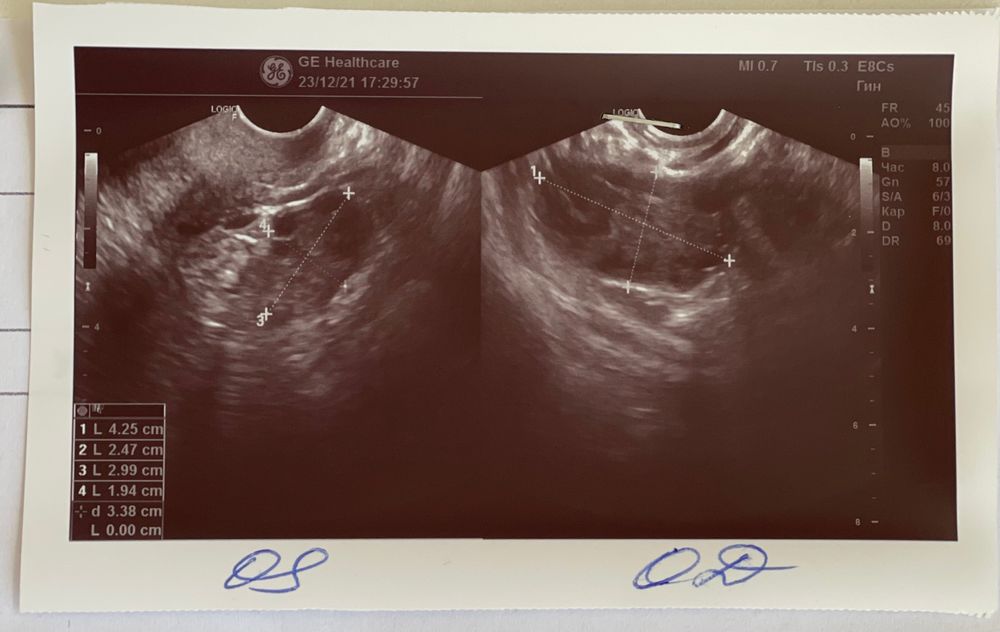

Добрый день) Была на узи на 21 дц (раньше не получалось, были в отпуске) Сначала врач сказала - фолликул 19 мм, потом спустя время сказала - жт, но точно не знает. Странно, я думала они различают:(Жидкость в позадиматочном пространстве нет.

Цикл скачет, в среднем 33-35 дней. По ощущениям овуляция была на 17-18 дц.

И все же, фолликул или жт?